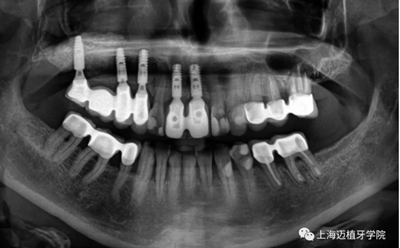

術(shù)后全景片,骨結(jié)合良好